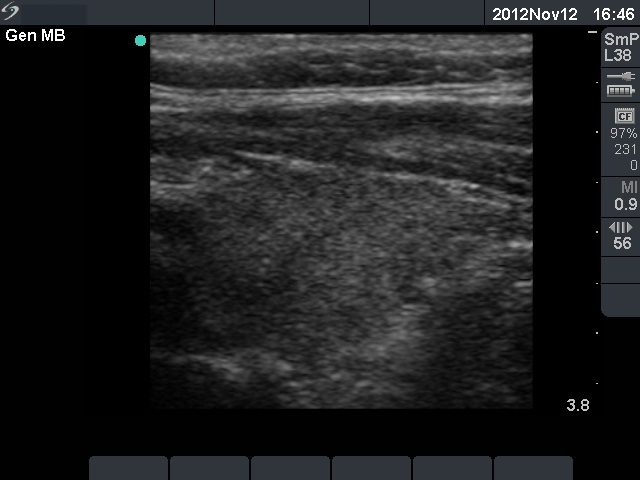

Follow-up examination 4 weeks later (3rd row of images):

He had no complaints with euthyroid hormone levels (TSH 2.41 mIU/L, FT4 14.1 pM/L) and normal CRP (1.1 mg/L) and ESR 9 mm/H.

Ultrasonography demonstrated an almost complete normalization.